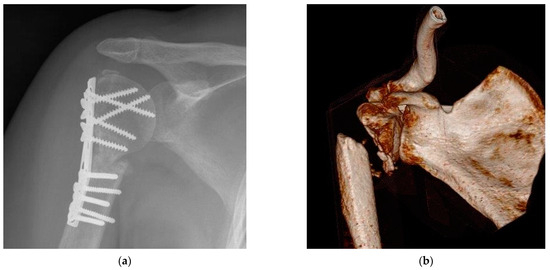

1.2. Transferability of Examinations on Gender Differences in Orthopedics

4. Materials and Methods

4.1. Group Formatting

4.2. Baseline Characteristics and Demographic Data

4.3. Fracture’s Severity and Previous Illness

4.4. Radiological Bone Healing Process